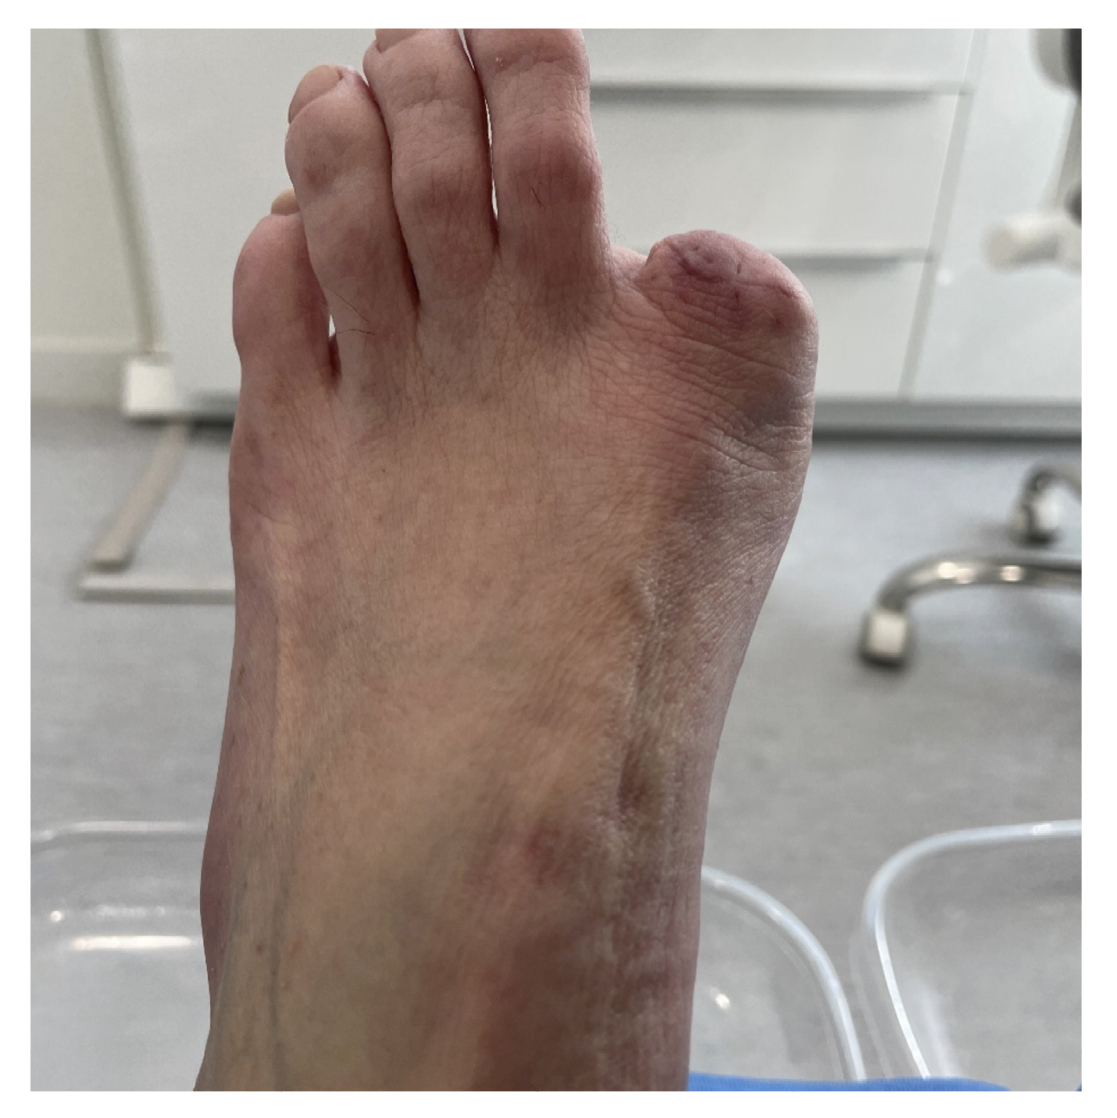

La paciente refiere proceso de inicial de onicocriptosis de 7 meses de evolución (septiembre de 2022), en el borde medial del primer dedo del pie izquierdo, con la presencia de tejido de granulación ungueal en dicho borde, el cual le produce dolor e inflamación digital (Figura 1). La paciente recibe tratamiento por su podólogo que consiste en quiropodia y limpieza del canal; se pautan posteriormente curas diarias con mupirocina para la lesión. Existe mala evolución de la lesión en los días siguientes con aumento de dolor y sensibilidad al tacto. Se modifica el tratamiento pautando amoxicilina/ácido clavulánico 875/125 mg, 1/8 h junto con el uso de analgésicos orales (Figura 2). La paciente continúa con mala evolución sintomatológica y acude a su centro de salud donde se realiza radiografía con la cual se descarta la presencia de infección profunda (osteomielitis).

Figura 2. Progresión clínica tras tratamiento ATB y analgésico.